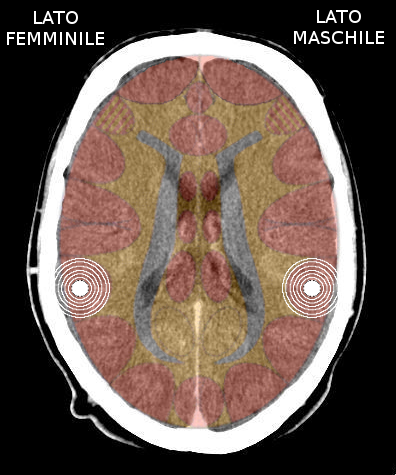

- Requisiti: Si è in costellazione schizofrenica quando due attivazioni colpiscono i due emisferi cerebrali di uno stesso livello:

- le due emiparti del tronco cerebrale;

- i due emisferi cerebellari;

- i due emisferi cerebrali (midollo e/o corteccia).

- NON È COSTELLAZIONE quando due attivazioni interessano due livelli cerebrali differenti, anche se occupano i due emisferi.